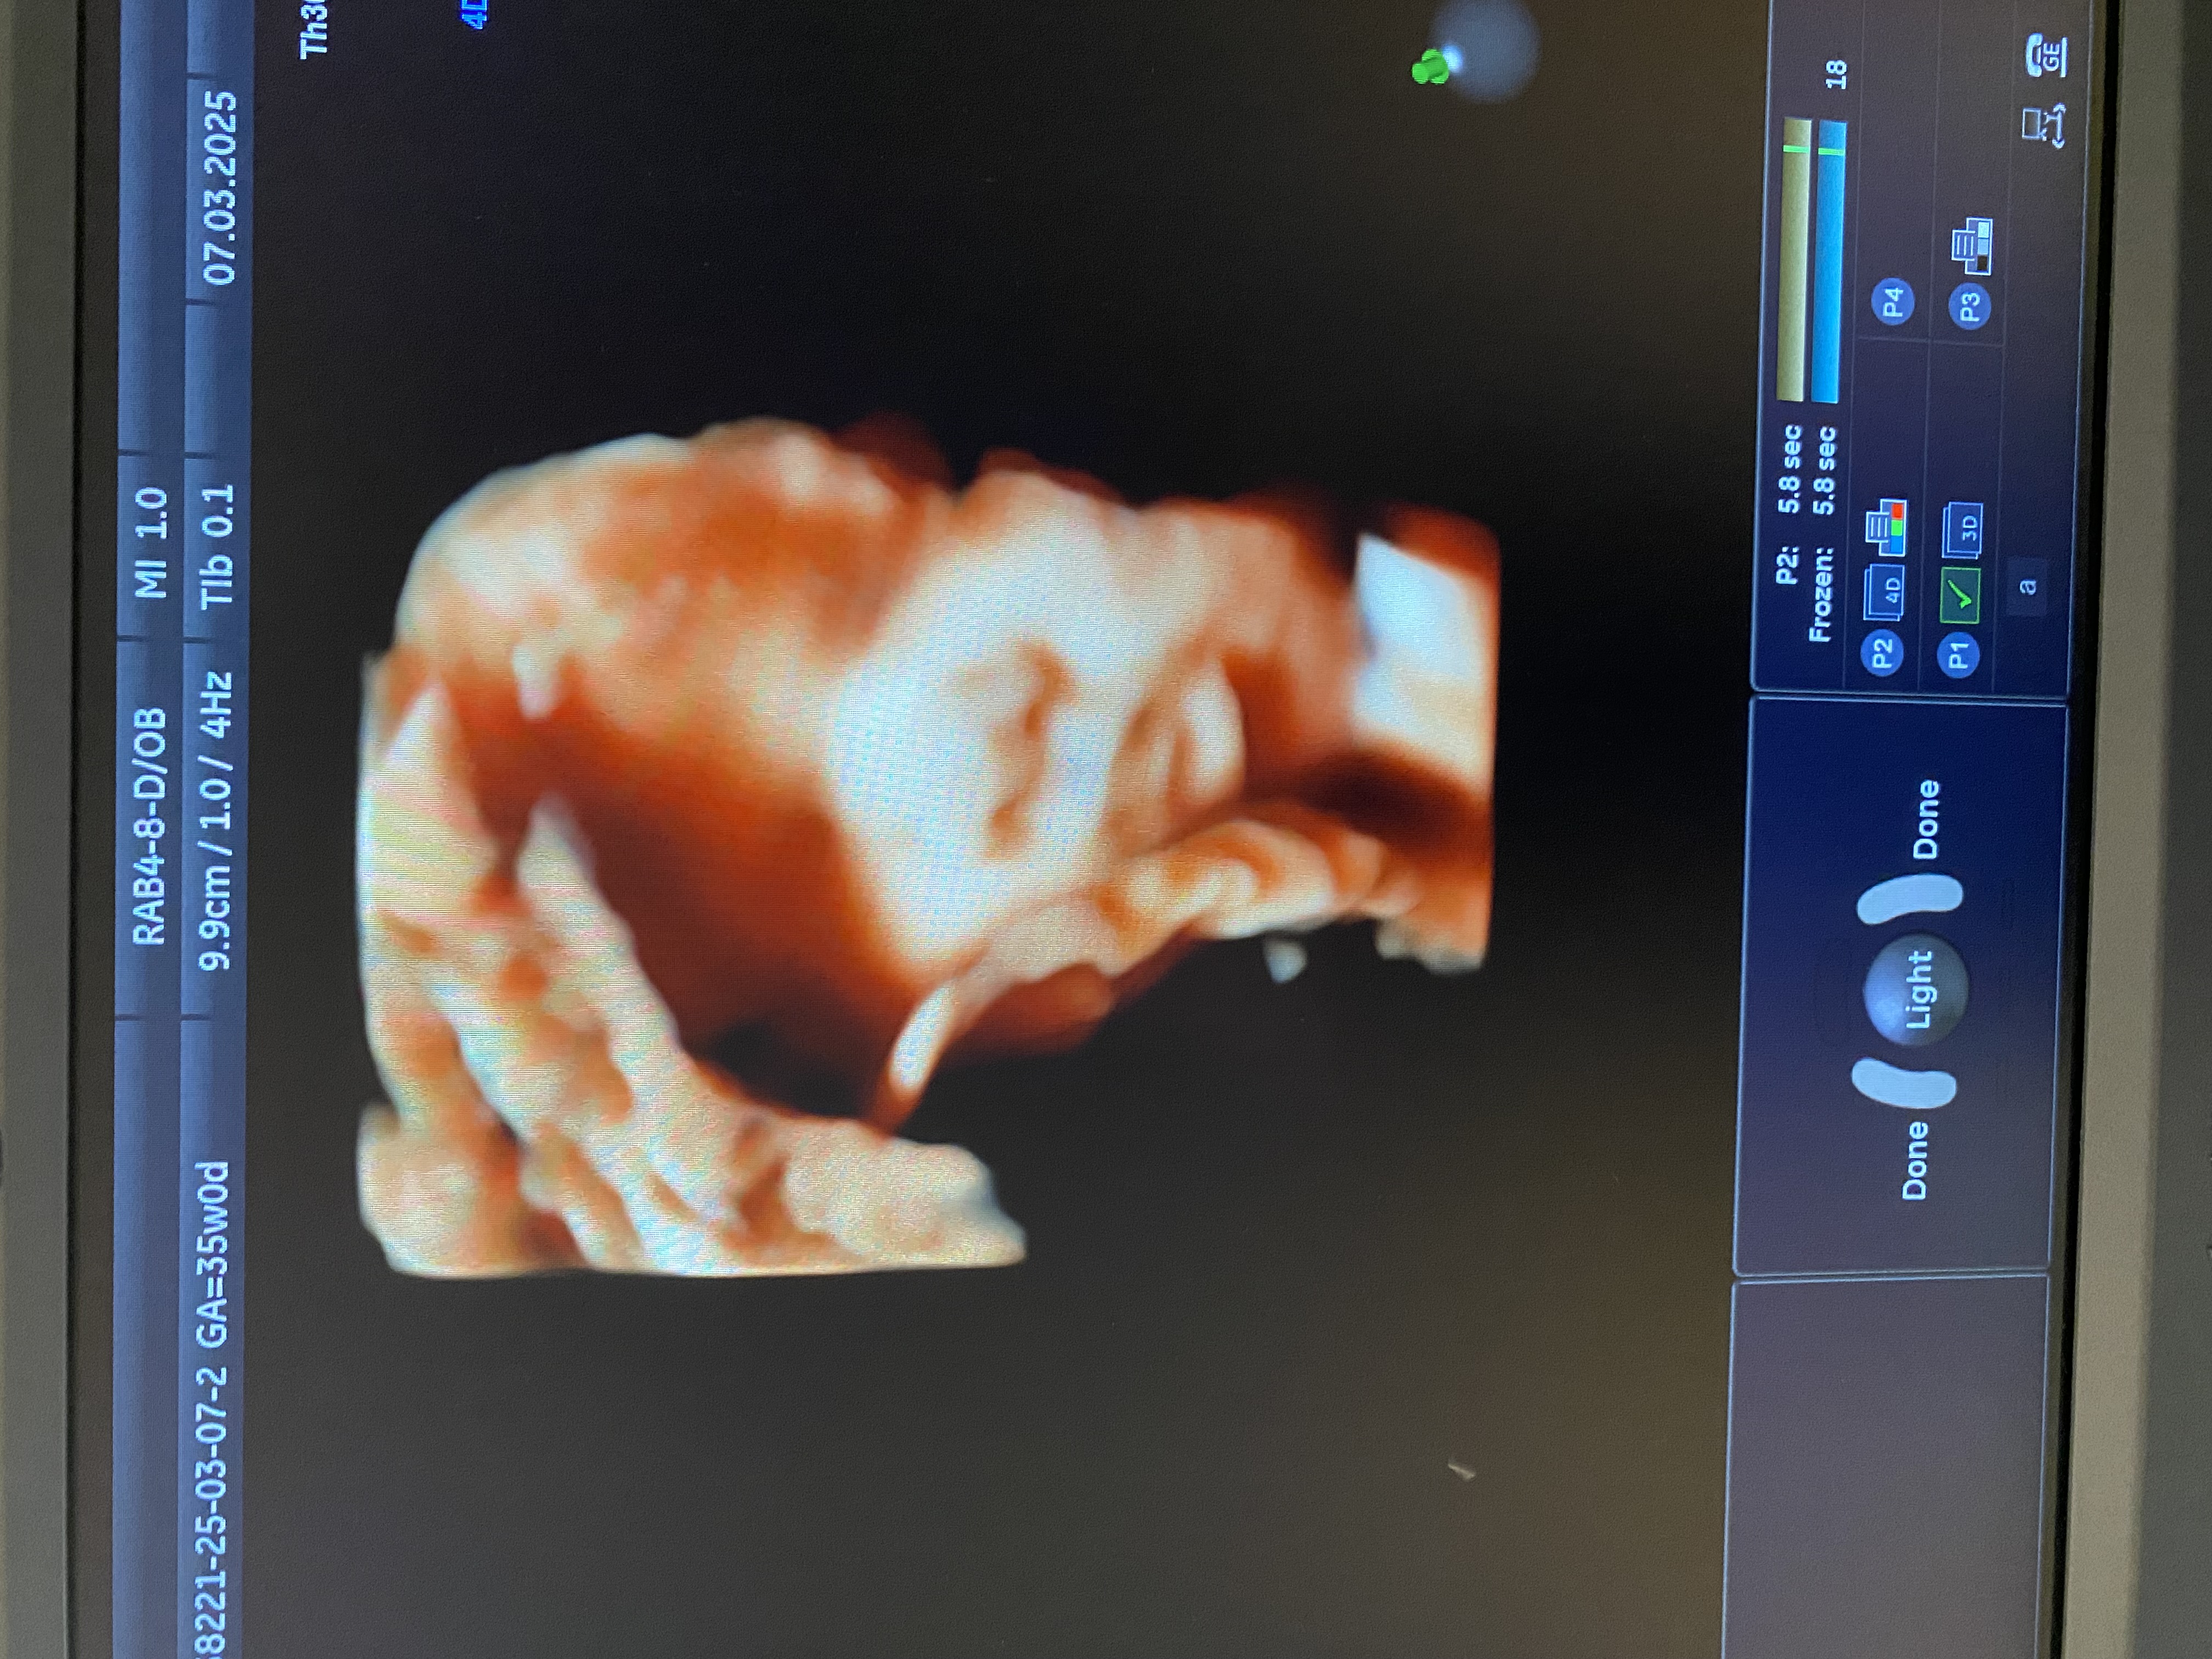

УЗИ. 35 недель и 4 дня

УЗИ, КТГ, доплерКакая она уже большая ☺️🥹. Вес 2570 грамм.

Это было первое УЗИ, на котором я уже перестала понимать где и что находится, такая она большая, разглядела только пальцы и голову😅